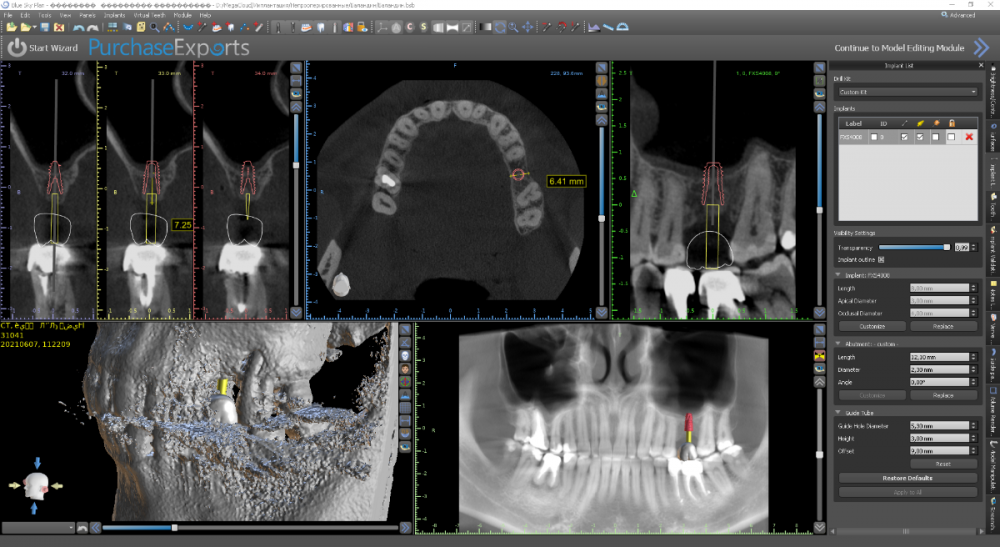

Женька Опубликовано 9 октября, 2021 Поделиться Опубликовано 9 октября, 2021 Коллеги здравствуйте. Планирую имплантацию, с синусом небольшим. Из анамнеза: зуб 2.6 ранее лечён в другой клинике. Попробовали перелечить и понаблюдать. Спустя полгода наблюдений вновь открылся свищевой ход. Приняли решение зуб удалять с последующей имплантацией. Собственно срок подошёл. Но на КТ дефект в области вестибулярной пластинки в проекции 2.7 никуда не делся (с чего бы). Отсюда вопрос. Раз уж всё равно будет разрез-лоскут-мягкие ткани. Стоит ли залезть и в эту область? Кмк может случиться швах с мягкими тканями из-за этого дефекта. Если уж залезать, то что делать? Убрать грануляции, обработать АБ+лидоксор, заполировать и ушить? Снимки до удаления и планирование. Разница 8 месяцев. Ссылка на комментарий

Женька Опубликовано 14 ноября, 2021 Автор Поделиться Опубликовано 14 ноября, 2021 Какой-то чудной зсл у меня получился... но это от недостатка опыта 100%. В общем фото сделал всего 2шт , скину в понедельник. Итак про ЗСЛ. Мой протокол: разрез, скелетирование, подшиваю лоскут для лучшей визуализации, далее пилотное дентиум не доходя 1-1.5мм, далее расширяю отверстие до нужного размера (здесь 3.8 имплантиум) и потом беру остеотом того же размера и стучим до появления "тупого" звука или ощущения "проваливания". Остеотомы у меня китайские, но со стоперами. Начинаю стучать и почти сразу чувствую, что провалился. Зондирую "зонтиком" - никакой эластичной подвижности... стучу ещё, тоже самое. Заметил, что стопер упирается проксимально в 2.7. Выкручиваю стоперы совсем. Стучу, звук особенно не меняется, но пациент отмечает неприятные ощущения. По остеотому 8мм (нативной кости 7 с копейками). Снова зондирую, снова не чувствую мембраны , пациент же говорит, что что-то есть, двигается будто. Решив, что хватит мучать бедолагу нарезаю пару столбиков Белкозина и пакую с помощью остеотома. Инсталирую имплантат и пациент отмечает чрезмерное распирание и легкую болезненность (еще 1.5 мм имплантата не погружено). Продолжаю глубить, всё спокойно. В итоге остановился на 1.5мм заглублении и заглушке, не рискнул ставить фдм, торк около 10). Вырезал сст, подшил вестибулярно и наконец-то закончил. Судя по РГ я подломил не только кортикальную пластинку, но и приличный кусок губки? Критично ли? После отметил лёгкую заложенность носа, без геморрагий. 4 Ссылка на комментарий